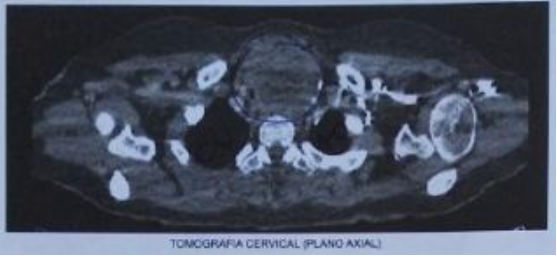

LESÃO QUE COMPRIME ESTRUTURAS ADJACENTES.

CONFIGURANDO COMO LINFOMA DE HO…LINFOMA DE TIREÓIDE OCORRE UM CRESCIMENTO MAIS RÁPIDO.